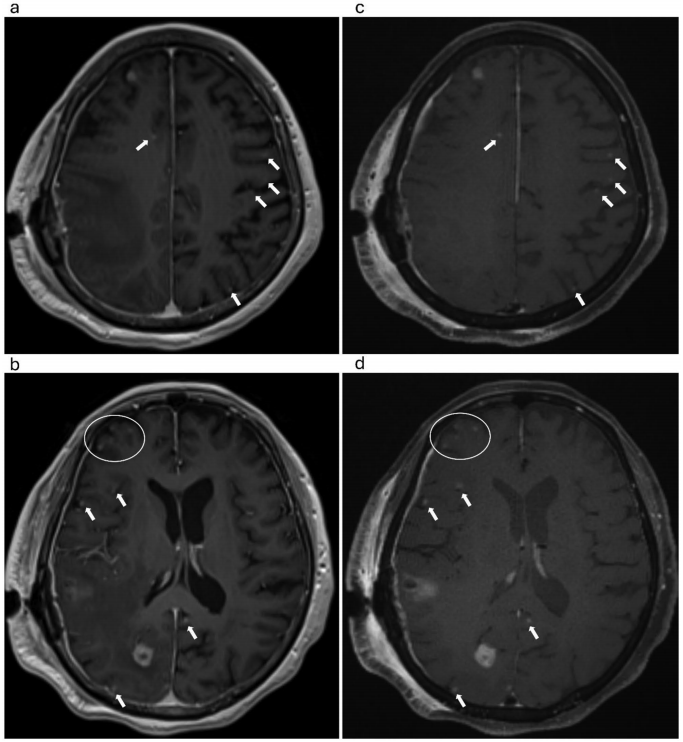

病灶检测能力方面,12%病例在SOS echo-uT1RESS上发现MPRAGE未显示的转移灶(直径2-3mm),如图3所示。

运动鲁棒性验证通过图2案例得以体现: